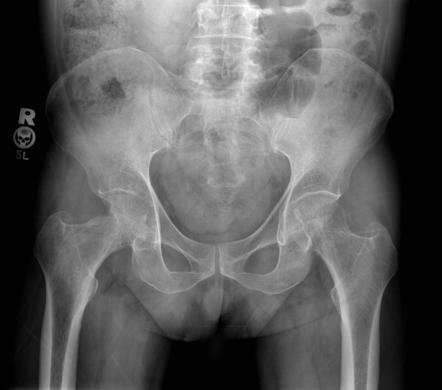

Туберкулёзное поражение тазобедренного сустава наблюдается наиболее часто среди всех крупных сочленений. Патологический процесс, как правило, начинается с костных эпифизов и распространяется на суставную капсулу и синовиальную оболочку. Рентгенологически на ранних стадиях определяется неравномерный остеопороз головки бедренной кости и вертлужной впадины, а также сужение суставной щели. В дальнейшем выявляются зоны субхондральной деструкции, узурация суставных поверхностей, деформация шейки бедренной кости и смещение суставных элементов. При прогрессировании возможен анкилоз, преимущественно фиброзного типа.

Тазобедренный сустав:

Субхондральный остеопороз головки бедренной кости и вертлужной впадины.

Сужение суставной щели с неравномерным просветом и асимметрией.

Очаговая узурация суставных поверхностей в зонах нагрузки.

Разрушение и деформация шейки бедренной кости.

Смещение головки бедра кнутри с укорочением конечности.

Формирование фиброзного анкилоза с полным исчезновением суставной щели.

Реактивное утолщение мягкотканных структур в проекции сустава.